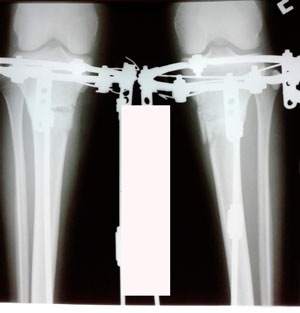

Исходник - 29 лет.

Дата операции - 11.03.2020

Вложения

image-11-03-20-10-08-2.jpg

image-11-03-20-10-08-1.jpg